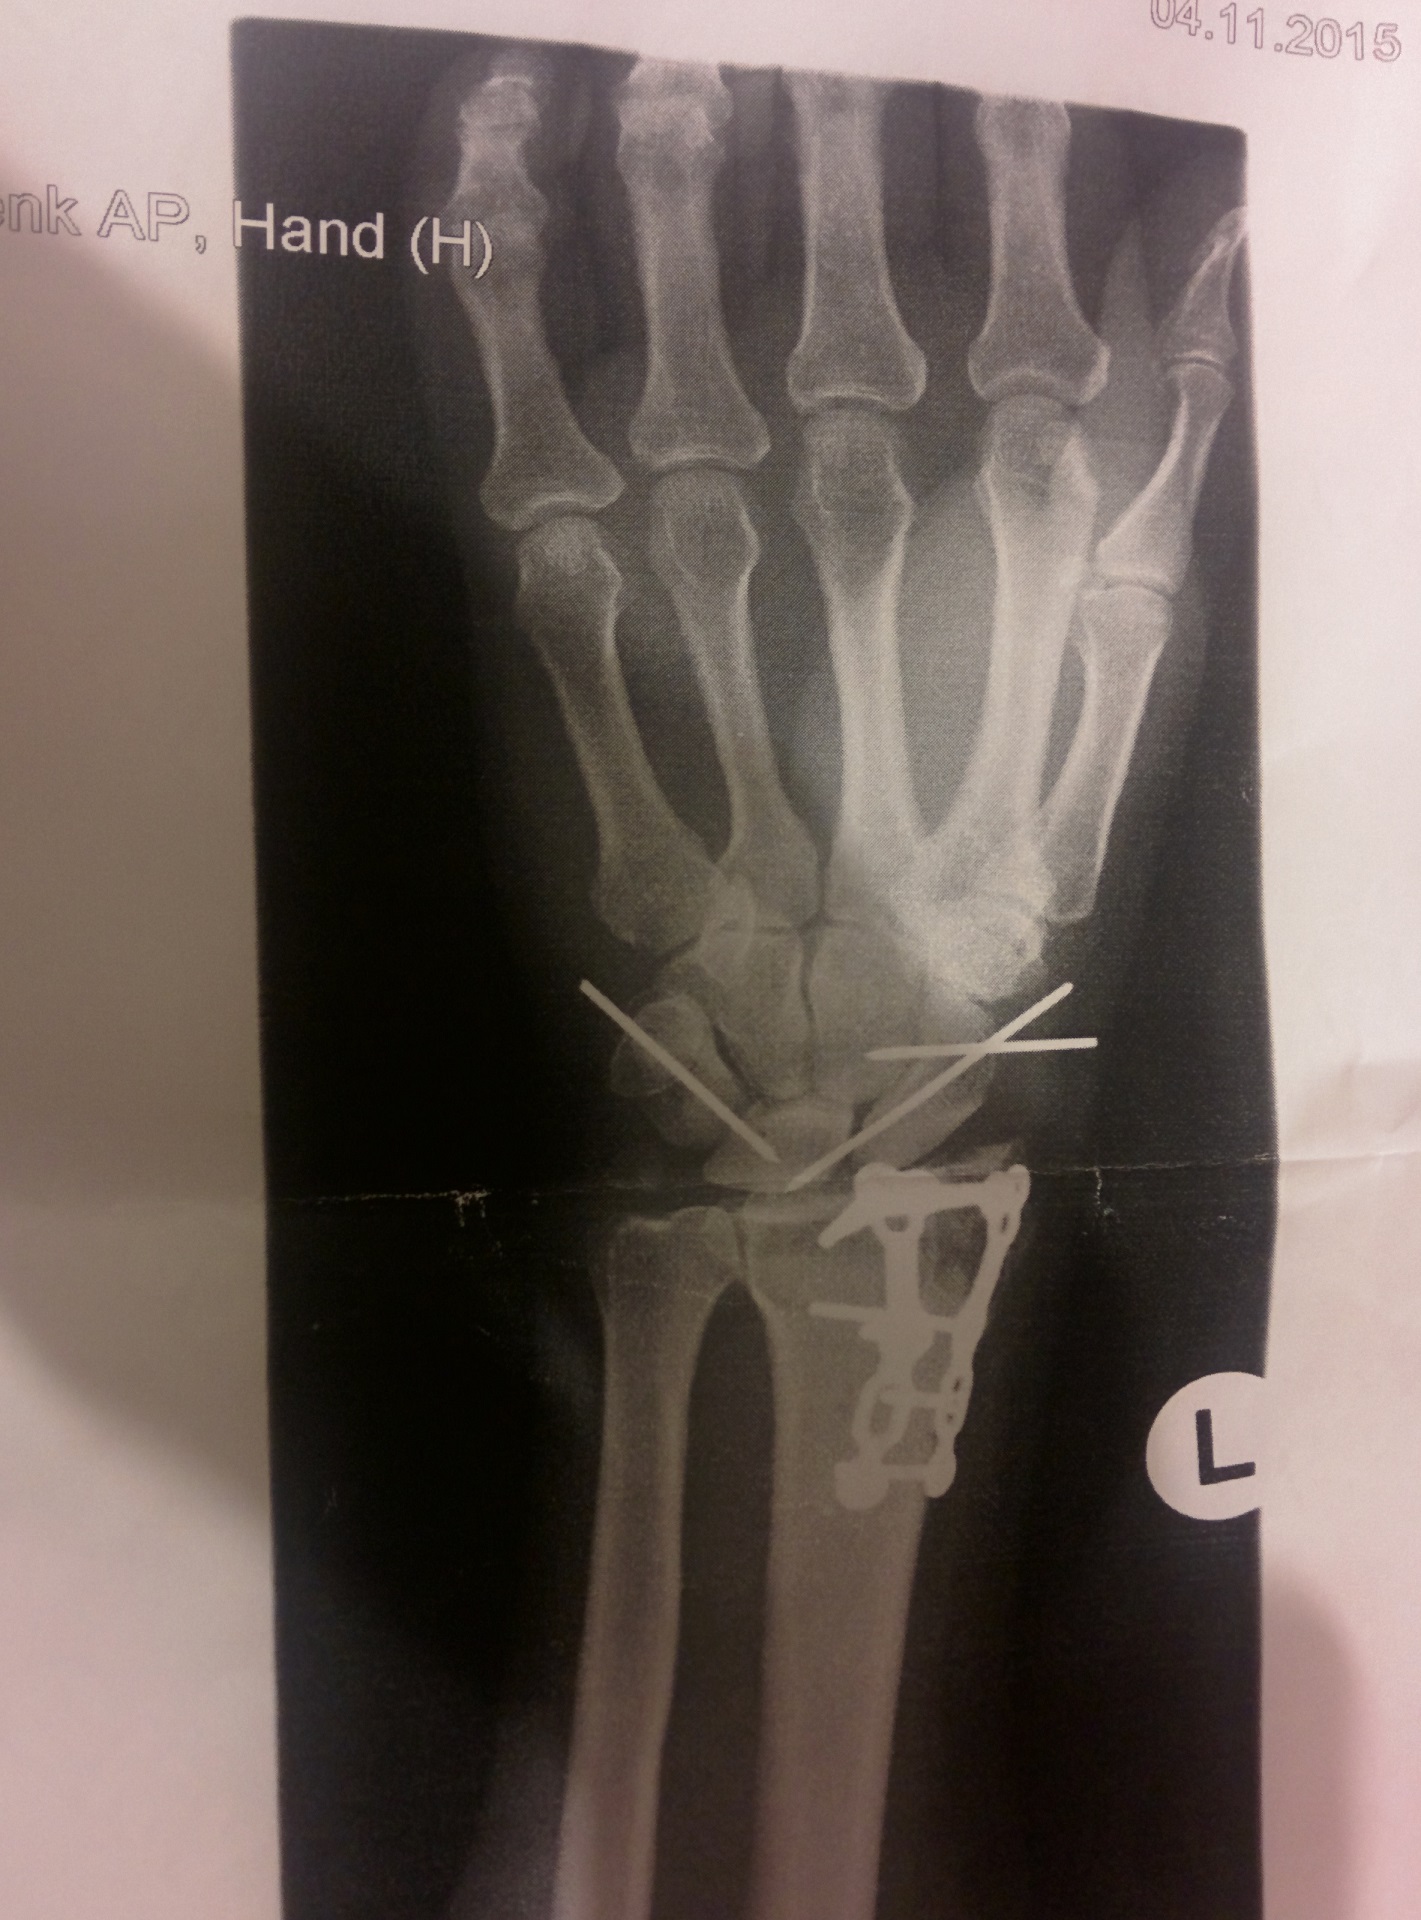

Die Brüche am rechten Arm verheilen gut und ich bekomme so mit der Zeit ein wenig Geschmeidigkeit in den gebeutelten Oberkörper

Diesen Monat muss ich noch zum Handchirurgen, mal sehen was der so sagen wird